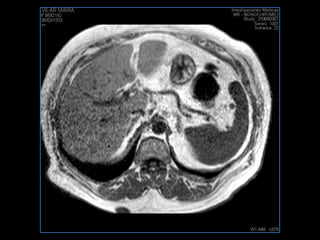

PROTOCOLO hígado graso AXIAL in phase y out phase AX T1 y AX fat sat +SAG T2  CON   GADOLINIO :  COR T1+AX T1(DIN) SAT: NO  FASE: RL THK: 4MM  COIL:  GAP: (FACTOR 1.4)  FOV: 40 CM NEX:2 SINCRONIZACION RESPIRATORIA EN 3 O 4 CICLOS ALE

resonancia de abdomen